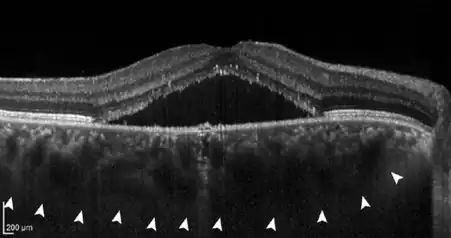

The disease mechanisms are not completely understood. All pachychoroid disorders of the macula show choroidal thickening and congestion with increased blood vessel diameter, especially in the deep choroid (the so-called Haller's layer). This results in increased pressure from the deep choroid against the superficial choroid close to the retina, damaging the fine blood vessels (capillaries) needed to supply oxygen and nutrients to the retinal pigment epithelium and retina. Additionally, fluid can leak from these damaged vessels and accumulate under the retina.[1][2]

- If the continuous congestion in the blood vessel system of the choroid causes pressure damage to its fine blood vessels (capillaries) and a continuous leakage of fluid in the direction of the adjacent Bruch's membrane and retinal pigment epithelium, the resulting damage in the pigment epithelium, which can be seen on funducsopy or retinal imaging, is referred to as pachychoroid pigment epitheliopathy (PPE). Patients with PPE usually have no symptoms.[3]

- If further damage to Bruch's membrane and the pigment epithelium causes fluid to accumulate under the retina, central serous chorioretinopathy (CCS) develops. In this stage, patients often have blurred vision and report a reduction in visual acuity with perception of a central "grey spot". In the majority of patients, spontaneous resolution of the subretinal fluid occurs within a few months, but recurs in up to 50% of cases. In some patients the fluid remains, making it a chronic disease; medical therapy or the application of various laser methods is possible.